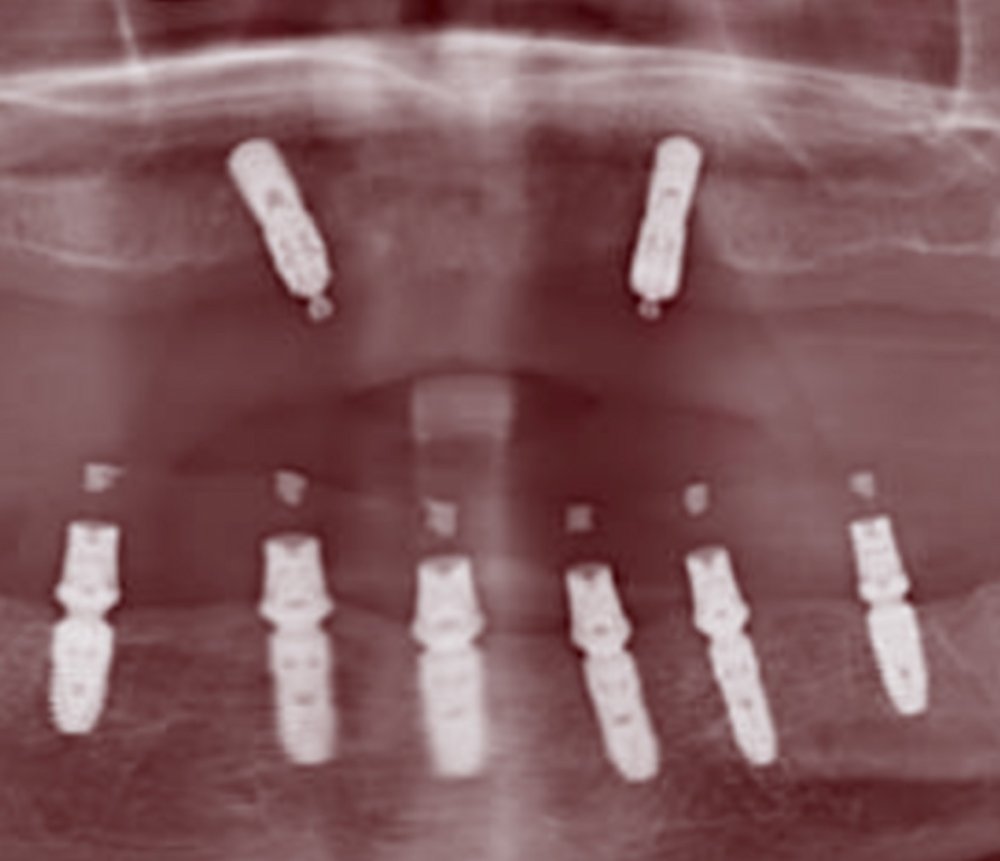

UPPER TEETH PROSTHETICS

2020